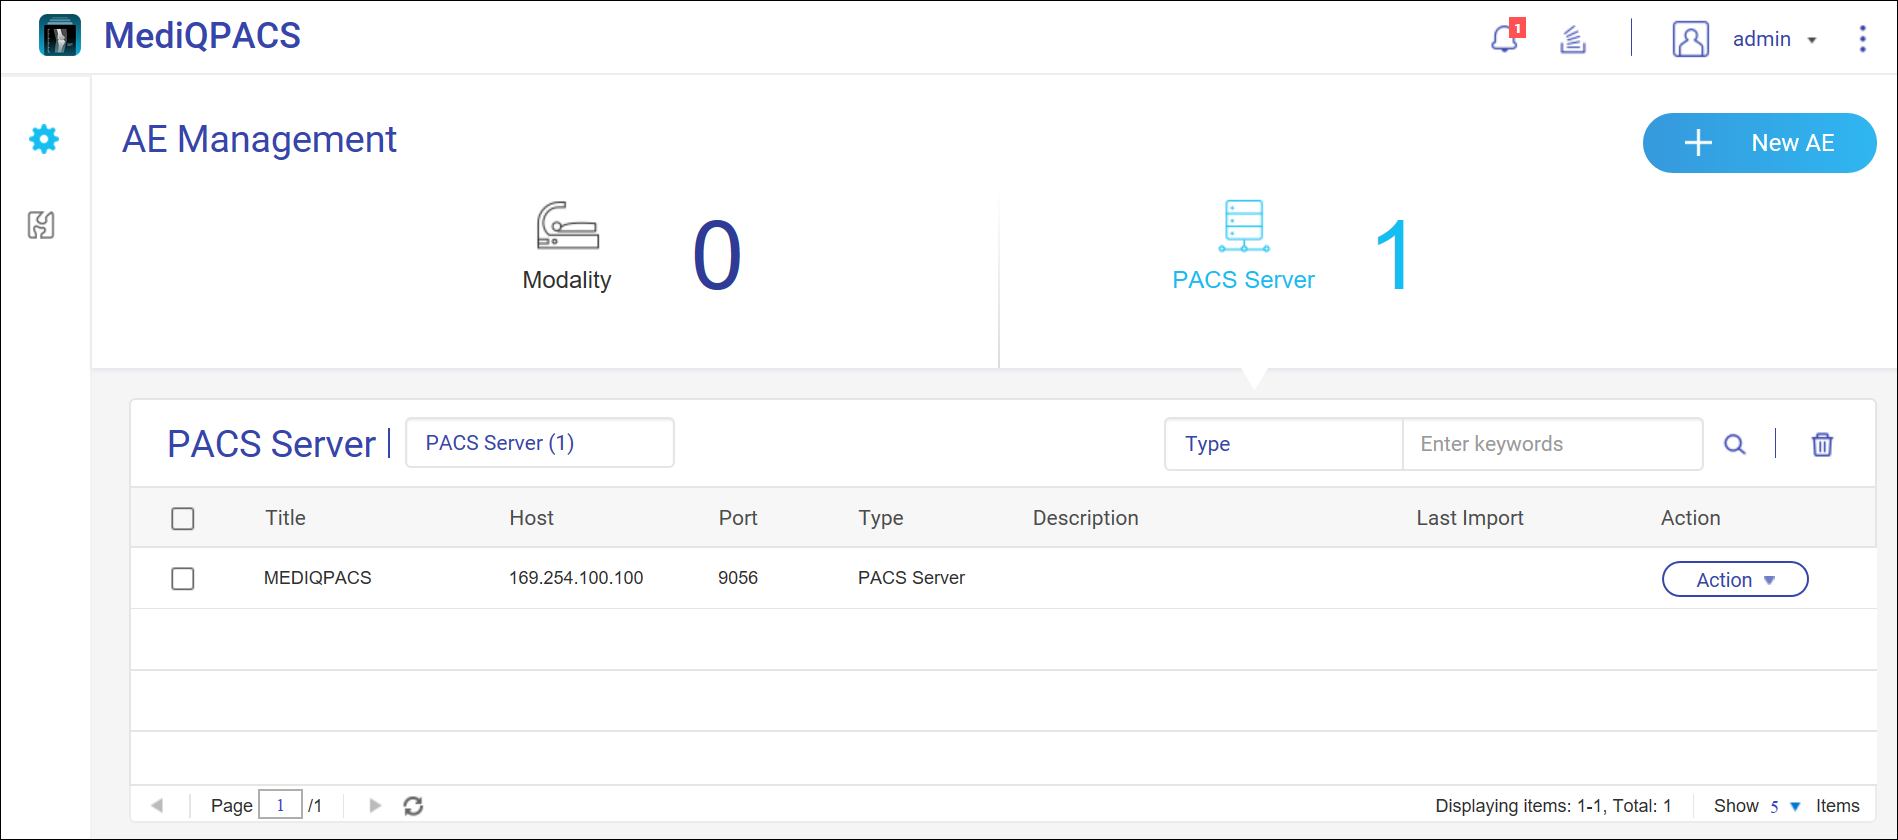

患者

用户可以搜索患者以查找相关 DICOM 图像和相关信息。

搜索患者

图像轮播

图像轮播显示为选定 PACS 服务器最新添加的 10 项患者研究。

选择 PACS 服务器,然后将鼠标指针悬停在图像上可查看研究和相应的图像系列。单击一个系列会在新的浏览器窗口中打开 DICOM Viewer。

指定设备类型和时间段可在图像轮播上显示相关研究。